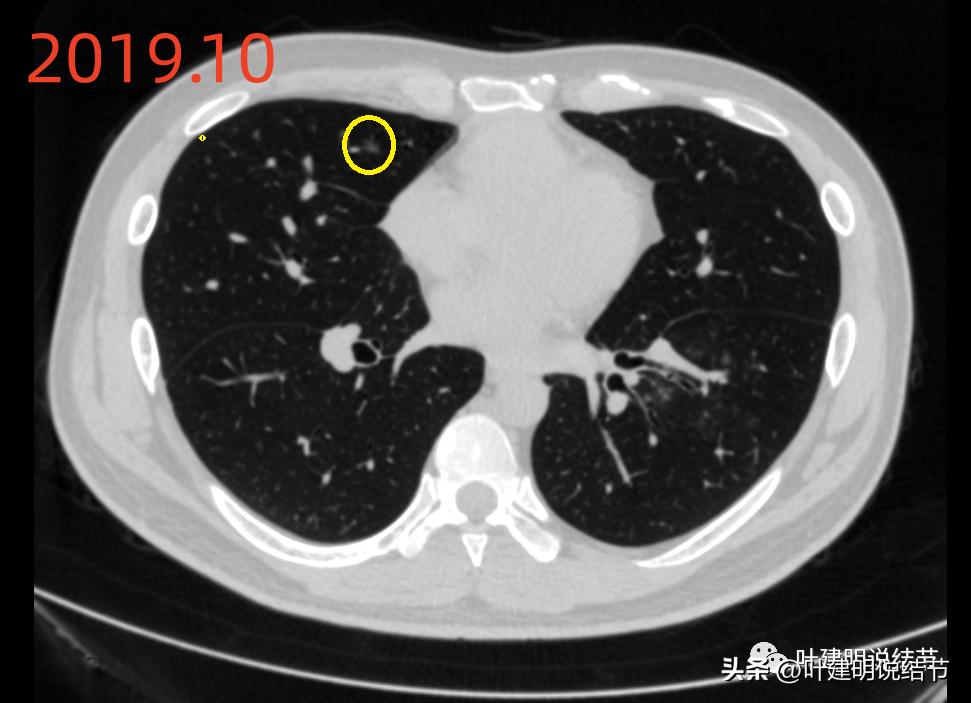

再看2019年时的影像:

病灶B当时也有,也是磨玻璃密度,轮廓清,有微小血管进入,应该仍考虑是肿瘤范畴的,只是也仍考虑不典型增生或原位癌可能性大,且前后对比无显著进展。

右中叶有淡磨玻璃结节(以下称病灶D),考虑慢性炎伴纤维增生或肺泡上皮增生可能性大。